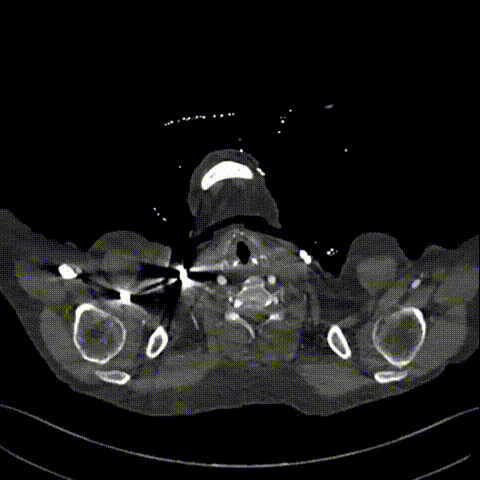

术后随访

患者出院前进行CTA复查,可见溃疡隔绝完全,弓上分支血管及冠状动脉通畅。

术后CTA

术后3D动态

术后3D动态 grey

术后3D重建